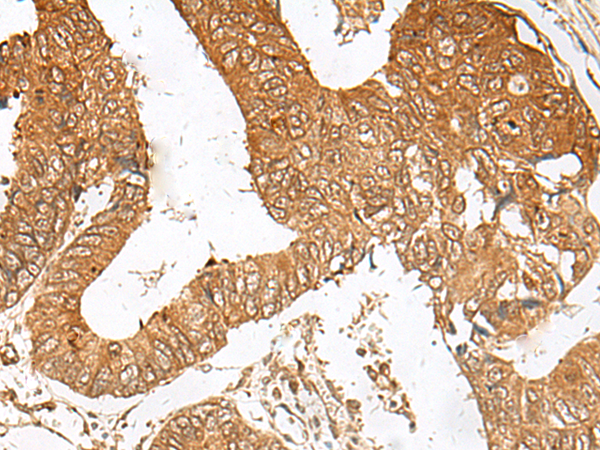

IHC (Immunohiostchemistry)

(The image is immunohistochemistry of paraffin-embedded Human cervical cancer tissue using 47251(ZBTB8A Antibody) at dilution 1/70.(Original magnification: 200))